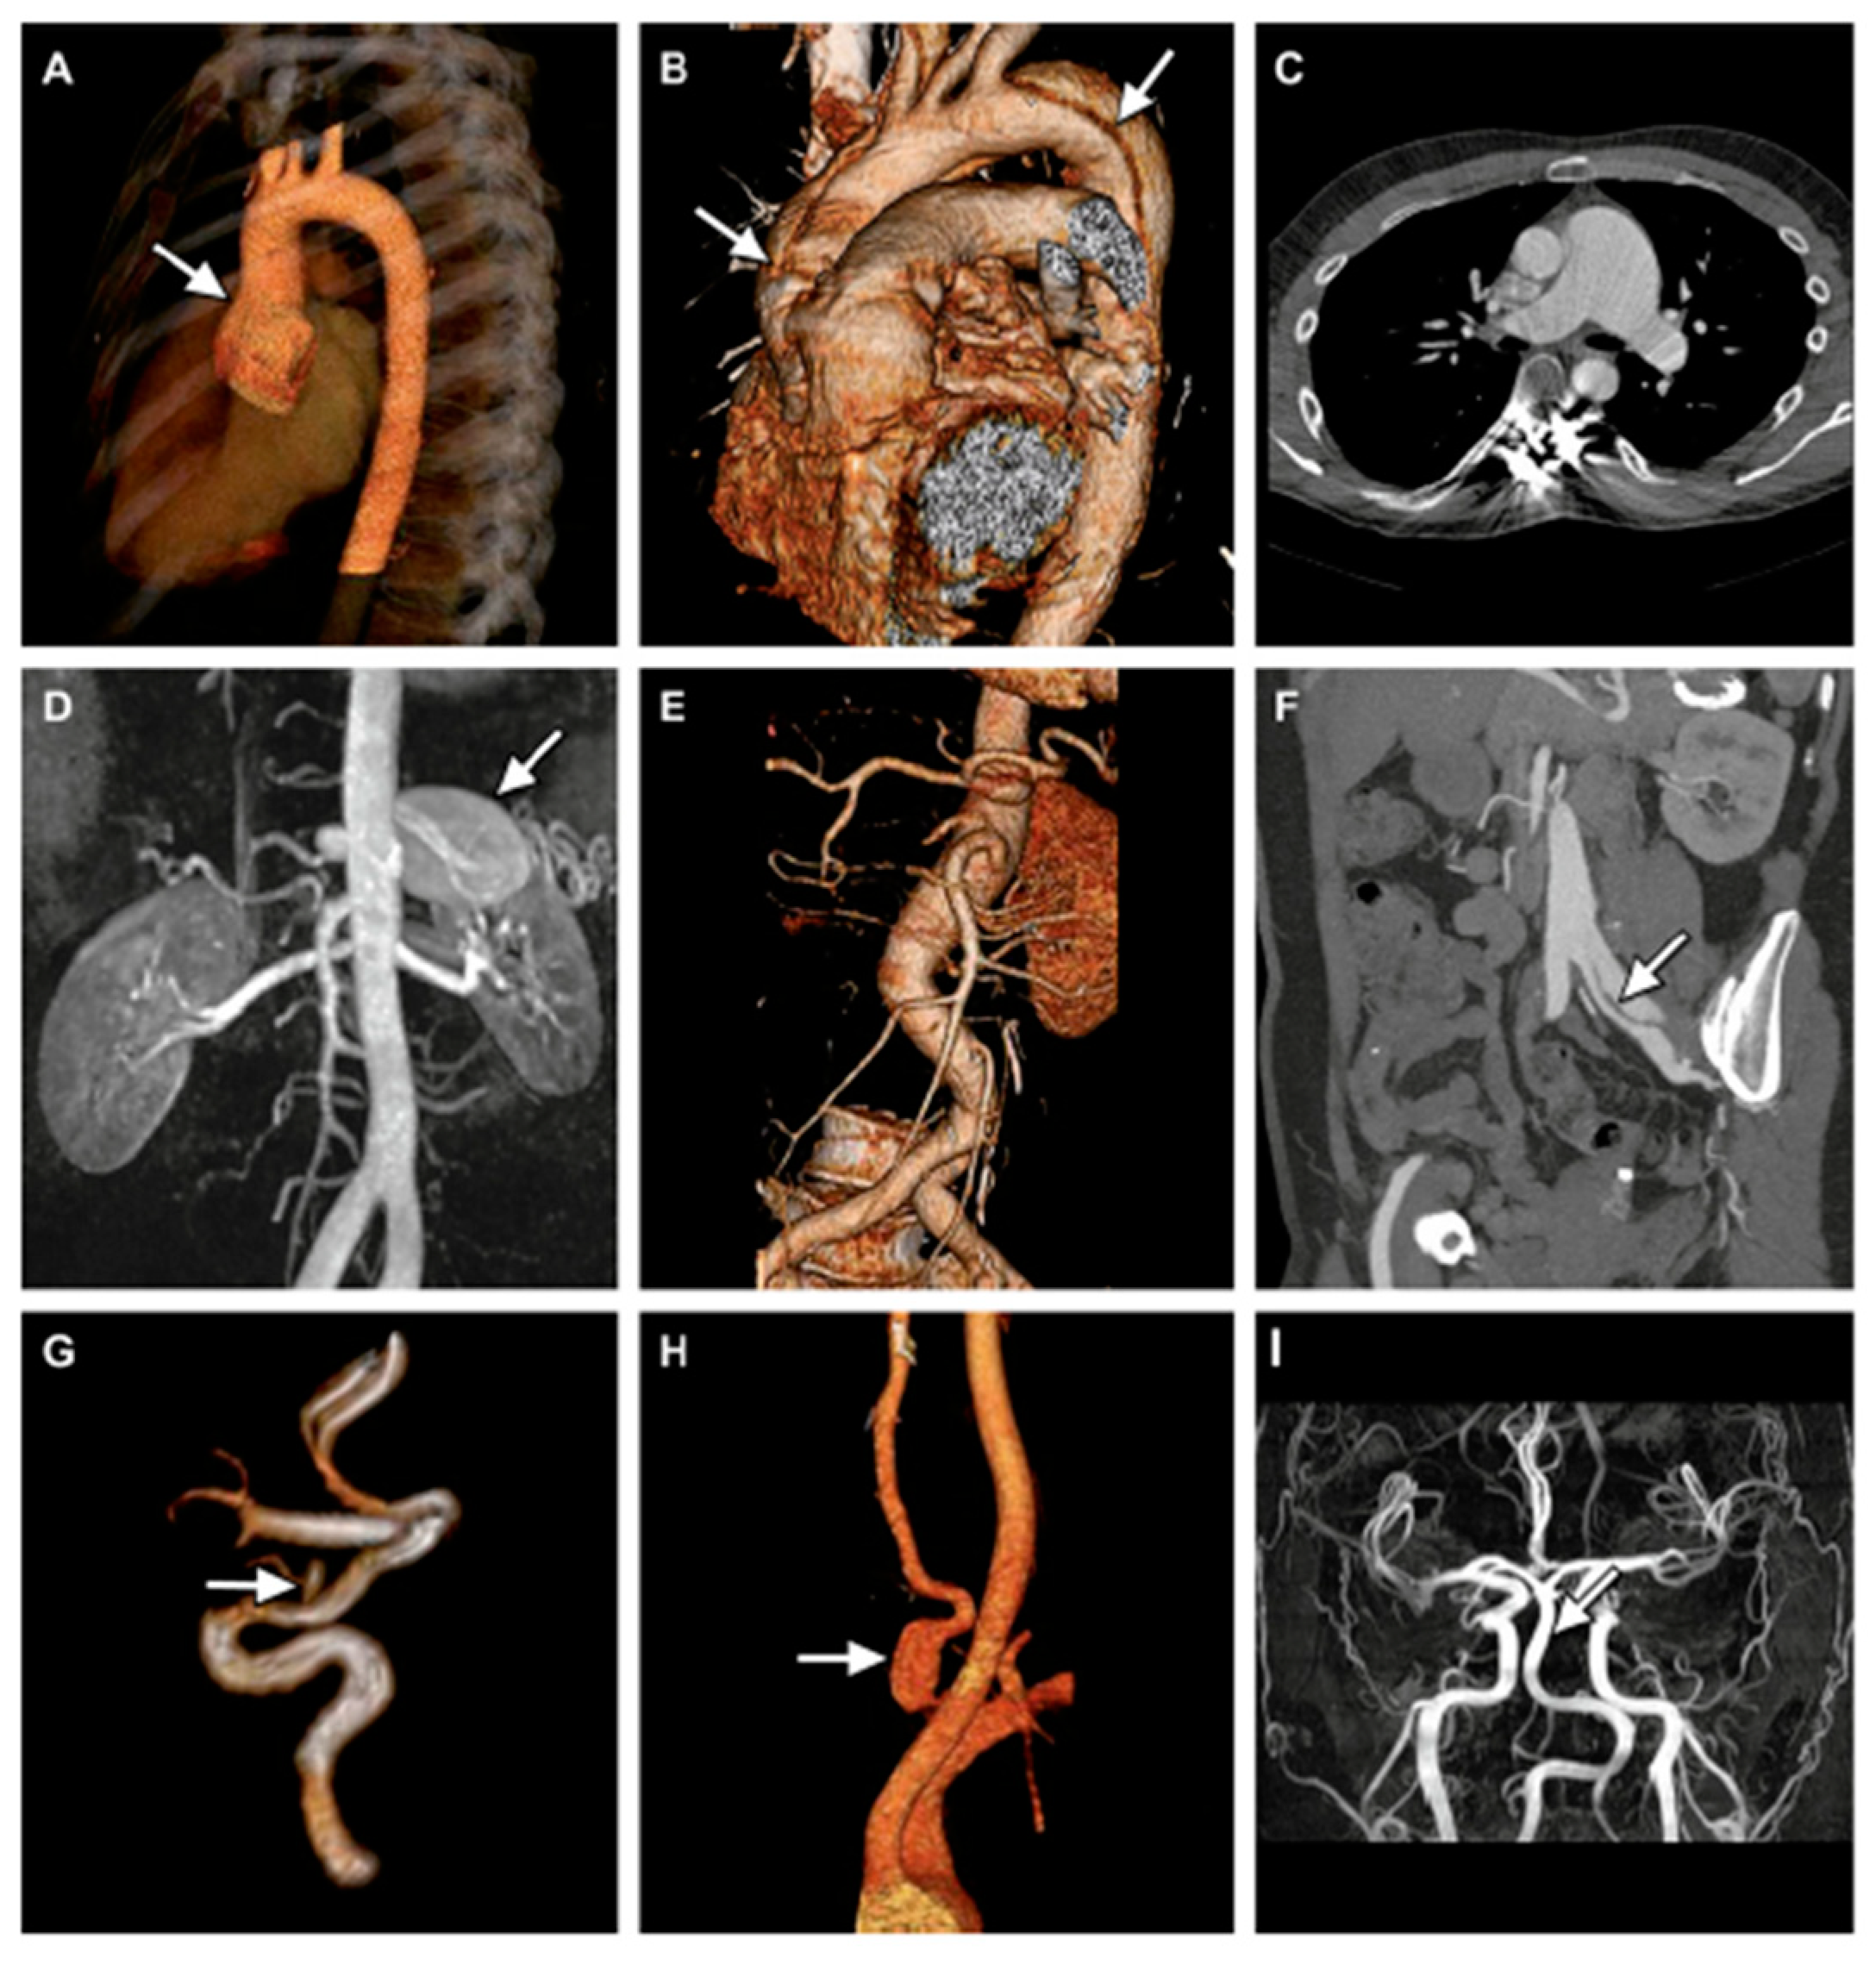

- Tijmes, F.S.; Karur, G.R. Imaging of Heritable Thoracic Aortic Disease. Semin. Roentgenol. 2022, 57, 364–379. [Google Scholar] [CrossRef]

- Meester, J.A.N.; Verstraeten, A.; Schepers, D.; Alaerts, M.; Van Laer, L.; Loeys, B.L. Differences in manifestations of Marfan syndrome, Ehlers-Danlos syndrome, and Loeys-Dietz syndrome. Ann. Cardiothorac. Surg. 2017, 6, 582–594. [Google Scholar] [CrossRef]

- Pepin, M.; Schwarze, U.; Superti-Furga, A.; Byers, P.H. Clinical and genetic features of Ehlers-Danlos syndrome type IV, the vascular type. N. Engl. J. Med. 2000, 342, 673–680. [Google Scholar] [CrossRef] [PubMed]

- Oderich, G.S.; Panneton, J.M.; Bower, T.C.; Lindor, N.M.; Cherry, K.J.; Noel, A.A.; Kalra, M.; Sullivan, T.; Gloviczki, P. The spectrum, management and clinical outcome of Ehlers-Danlos syndrome type IV: A 30-year experience. J. Vasc. Surg. 2005, 42, 98–106. [Google Scholar] [CrossRef] [PubMed]